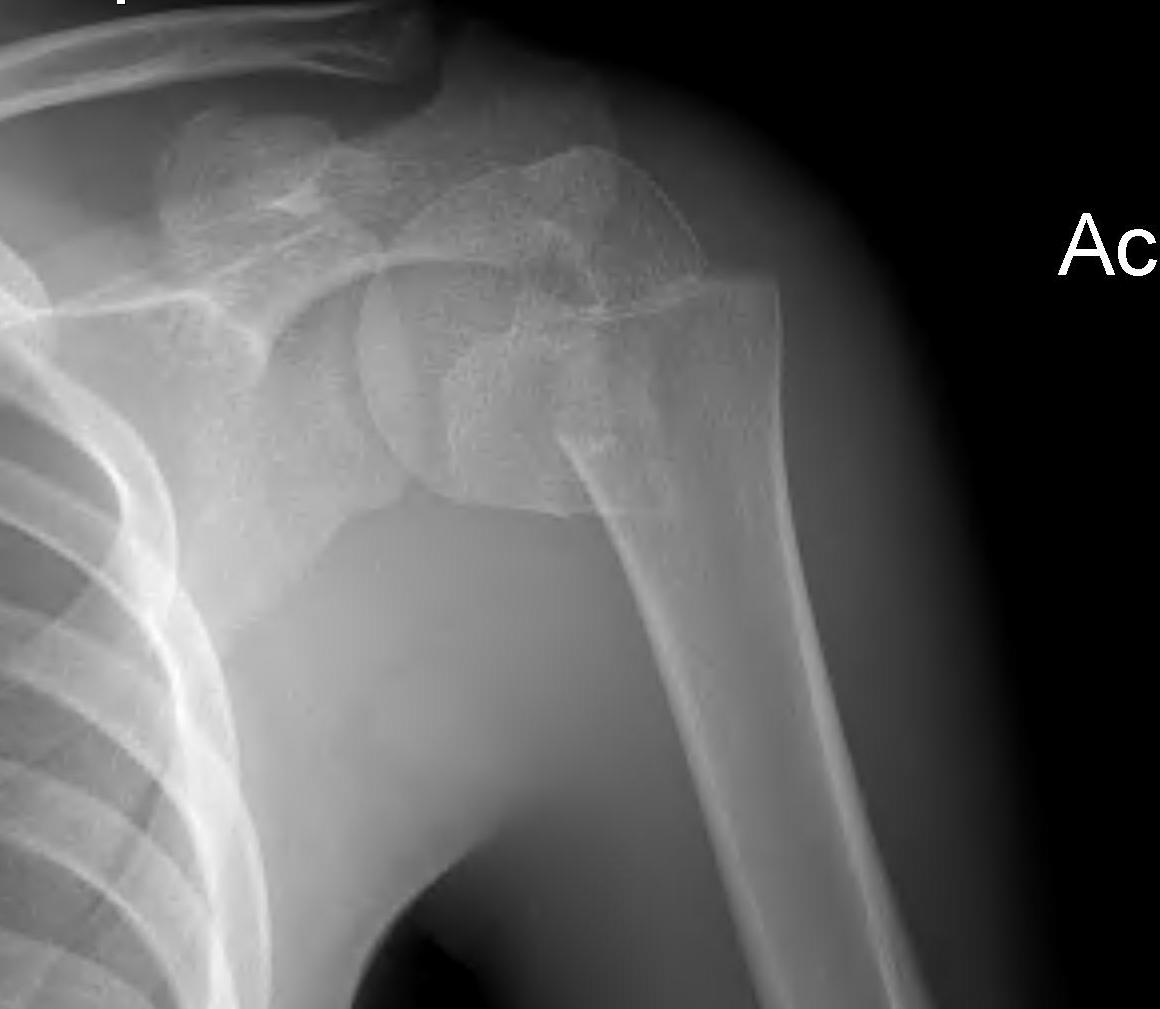

Case: 18 year old boy

Initial xray 18 month xray